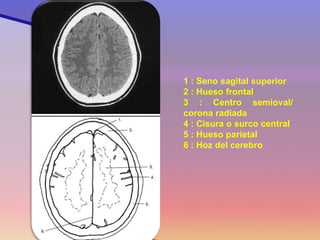

1 : Seno sagital superior 2 : Hueso frontal 3 : Centro semioval/ corona radiada 4 : Cisura o surco central 5 : Hueso parietal 6 : Hoz del cerebro

1 : Senosagital superior 2 : Hueso frontal 3 : Centro semioval/ corona radiada 4 : Cisura o surco central 5 : Hueso parietal 6 : Hoz del cerebro